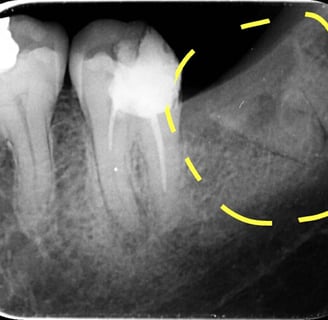

Radiografiile retroalveolare sunt concepute pentru a oferi imagini detaliate ale regiunii alveolare, care conține rădăcinile dinților și structurile osoase adiacente. Aceste radiografii se realizează în principal pentru a evalua sănătatea rădăcinilor dentare și pentru a detecta eventuale afecțiuni sau probleme din acest domeniu.

Evaluarea rădăcinilor dentare: Aceste radiografii sunt esențiale pentru evaluarea stării rădăcinilor dentare, identificarea leziunilor sau a altor probleme legate de rădăcini.

Identificarea afecțiunilor osoase: Aceste radiografii pot ajuta la identificarea afecțiunilor sau a problemelor osoase din regiunea alveolară.

Diagnosticul leziunilor endodontice: Aceste radiografii sunt esențiale în diagnosticul afecțiunilor pulpare și pentru ghidarea tratamentelor endodontice.

Evaluarea rădăcinilor dinților: Radiografiile retroalveolare ajută la evaluarea stării rădăcinilor dentare și la detectarea eventualelor anomalii.